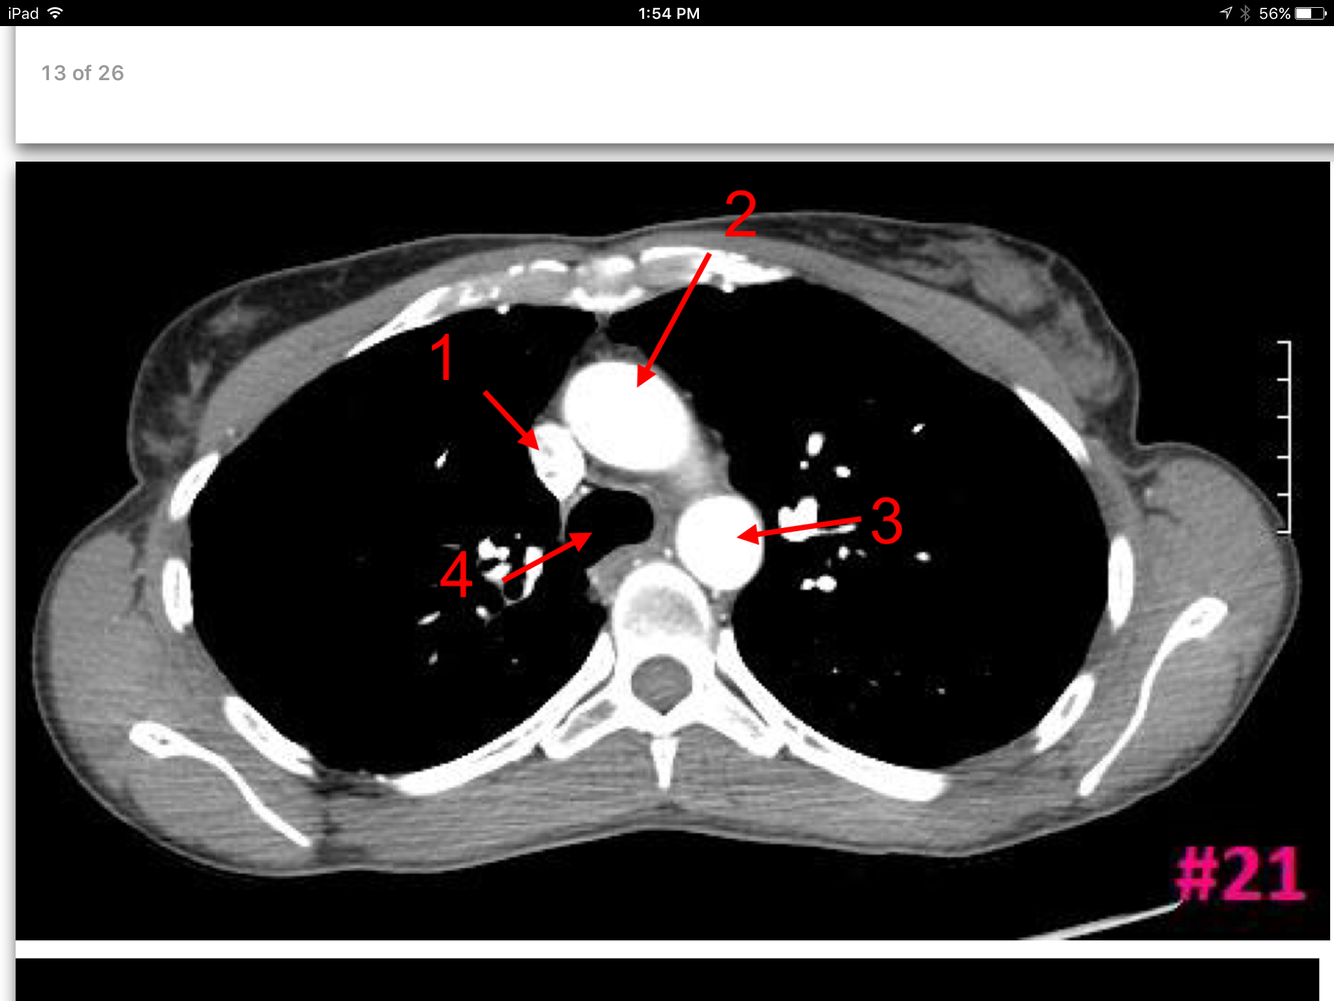

13

Q

A

Superior vena cava

Ascending aorta

Descending aorta

Trachea

Parietal pleura

Visceral pleura

Pulmonary vessels